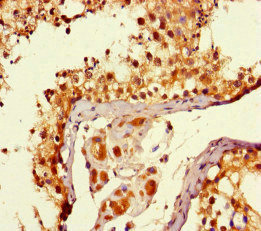

Immunohistochemistry of paraffin-embedded human testis tissue using CSB-PA008968HA01HU at dilution of 1:100